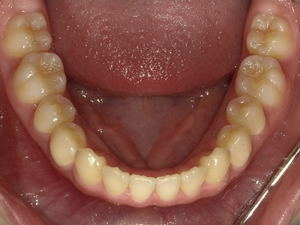

すきっぱ(空隙歯列)CASE5 2023.06.19 10代女性非抜歯〇ご相談内容:上前歯のすきっぱ〇矯正の種類:マウスピース型矯正「インビザラインGO」〇治療期間:14週間〇治療費用:44万円(税込) < すきっぱ(空隙歯列)CASE6すきっぱ(空隙歯列)CASE4 > ブログ記事一覧をみる